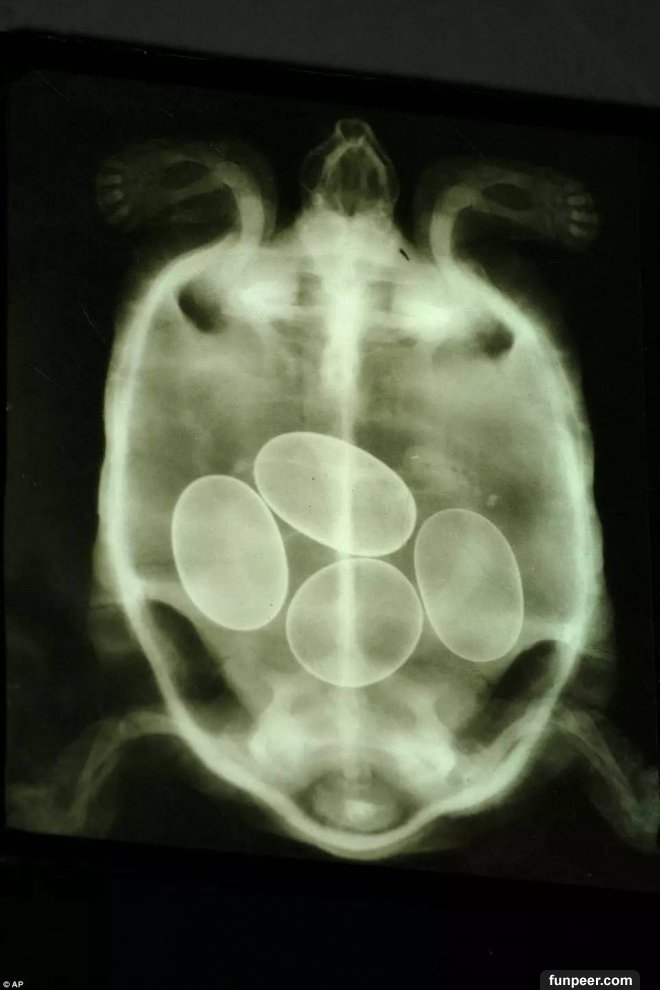

烏龜的X光照片,裡面有四隻蛋